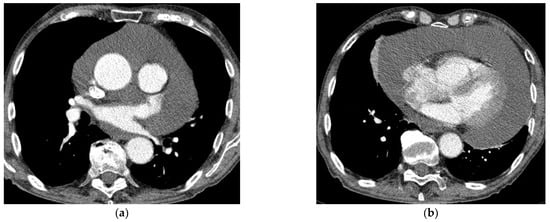

Chest CT

Chest CT examination was performed using a 128-slice GE Revolution GSI scanner (General Medical Equipment SAL, Bauchrieh, Lebanon). The examinations were usually provided monophasically with the administration of iodine contrast agent in an amount adjusted to the patient’s weight. A contrast administration delay of 25 s was used for routine chest examination. In the case of emergency, CT examinations were often performed in a CTPA protocol (CT Pulmonary Angiography) with a smart-prep or bolus test technique. The contrast was not used in the patients with renal insufficiency, iodine sensitization, or a history of allergic reaction to contrast (Figure 2a,b).

Figure 2. (a,b) Chest CT with contrast enhancement shows a large pericardial effusion.

It is very important to perform chest CT before the surgical procedure in the group of patients who do not require immediate pericardial decompression. CT provides important information, allowing the detection of pericardial loculations, cysts, pericardial thickening and masses, and associated chest abnormalities [1,14]. Thus, it may help to determine the possible cause of LPE, as well as the feasibility of surgical drainage. Moreover, it provides valuable information on the composition of the fluid based on the attenuation values (Hounsfield units (HU)) [1,14]. Attenuation values < 10 HU denote transudative fluids, while those >10 HU indicate exudative ones. Values between 20 and 60 HU suggest a purulent or malignant cause and values >60 HU suggest hemorrhagic fluid. In cases of chylopericardium, values of −60 to −80 HU are reported [1,14]. In our group of patients, CT was performed before the intervention in 35 patients. Chest MRI was rarely performed in our institution in the diagnostics of LPE. The long duration of the study limited its applicability in patients who were unstable or required monitoring. In the present study group, it was performed in only three cases.